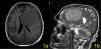

Case: A 60-year-old man admitted to the emergency department with generalized convulsion. In the cranial MRI, a 70×65×62 mm-sized lesion was detected in the left frontal lobe with a more prominent contrast enhancement at the center of the lesion (a significant finding for lymphoma) (Figure 1a,b). In his clinical history, cognitive, depressive, and behavioral symptoms were prevalent. His primary symptoms were irritability, loss of interest, apraxia, and amnesia. He was diagnosed with dementia and depressive disorder. A typical antipsychotic and an antidepressant drug were started in the psychiatry department. He continued this treatment for three months until his first seizure.